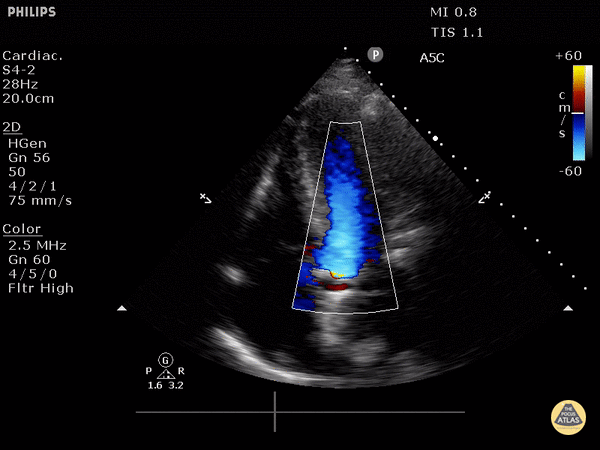

https://www.thepocusatlas.com/valvulopathy